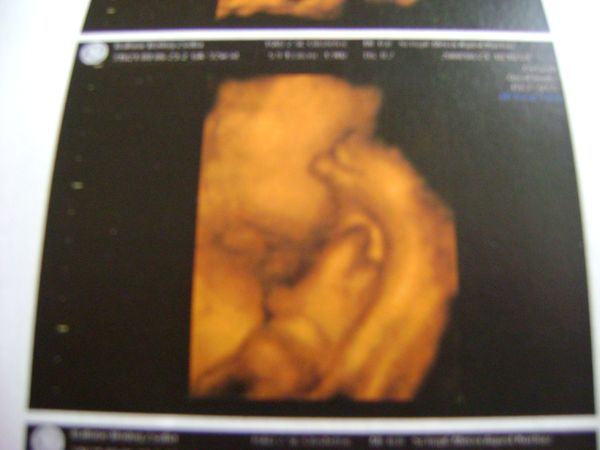

na és akkor jöjjenek a képek! :) alatta a terhességi hét a mensi szerint...

Kép

beni_18w0d_kisbabas

beni_23e4d_gondolkodos

beni_23w4d_bizonyitott_kisfiu

beni_29w0d_cumizos

beni_29w0d_pisze_nozi

beni_32w3d_izmoska

beni_32w3d_kezes_labas

bocsi, hogy sok voltam... az én véleményem szerint, azért a 18. heti még olyan kis ufós... vagy nem? főleg így 4d-ben... az azért hozzátartozik, hogy nekem eléggé vastag a hasfalam, meg háj is van rajta, szóval lehet, hogy másnak szebbet tudnának csinálni ennyi idősen... :)